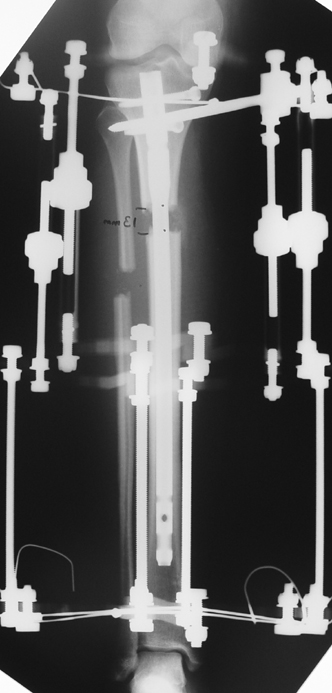

The application of the external fixator: Three Schanz screws are placed distally and three screws are placed proximally. At least 1 mm of distance shall remain between the screws and the nail.

In selected cases, we prefer to use a combination of a unilateral dynamic axial fixator and an interlocked intramedullary nail, in order to protect the length and alignment after the completion of the lengthening procedure. As a prerequisite for this technique, the narowest diameter of the medullary cavity shall be wider than 7 mm and the length of the nail segment distal to the osteotomy site shall be at least 8 cm. after the completion of the lengthening procedure.The intramedullary nail neutralizes shear and bending forces on femur during lengthening, shortens external fixation time, and protects newly formed bone against fractures. In our series, subtrochanteric osteotomy was performed in one case. No varus angulation occured despite the intramedullary nail.

Ilizarov stressed the significance of endosteal blood circulation for distraction osteogenesis. Although we placed the intramedullary nail after reaming the femur in all cases, the time for callus formation was not longer than expected. Thus we found that there is no slowing in the rate of new bone formation due to disruption of medullary blood flow. The rationale of this finding is revascularization that occurs following reaming of the medullary cavity, the fixation stability with the intramedullary nail and early functional weight bearing. The potential disadvantages of a combined use of external and internal fixation metods are increased blood loss, intramedullary infection, risk of fat embolism and excessive metal load.The most fearsome complication is a deep intramedullary infection (panosteomyelitis) triggered by pin tract infection.No such complication was encountered in our series. In order to avoid this complication, after the completion of lengthening the nail shaill be interlocked from the medial side, and contact of internal and external fixator pins shall be avoided.